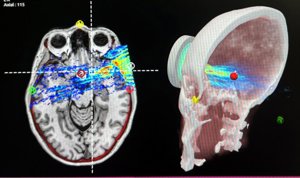

Como parte del concurso, Kimera Labs se ha asociado con el Dr. Sheldon Jordan y el Proyecto Regenesis para combinar su tecnología de exosomas perinatales hiperaislados con ultrasonidos focalizados de baja intensidad dirigidos al cerebro. Esta novedosa plataforma ha mostrado prometedores resultados preclínicos, publicados por el grupo en Nature Scientific Reports en octubre de 2023, que abren el potencial para mitigar enfermedades relacionadas con la edad, promover la regeneración tisular y mejorar la vitalidad general.

El Proyecto Regenesis del neurólogo Sheldon Jordan MD participa activamente en numerosos estudios de investigación clínica que proporcionan a los pacientes acceso a modalidades terapéuticas de vanguardia, como ultrasonido focalizado, TMS y fototerapia. Nuestros ensayos clínicos en curso abarcan afecciones como la demencia, la enfermedad de Parkinson, el traumatismo craneoencefálico, la ansiedad, la depresión y el TOC, así como el dolor crónico y el coma.